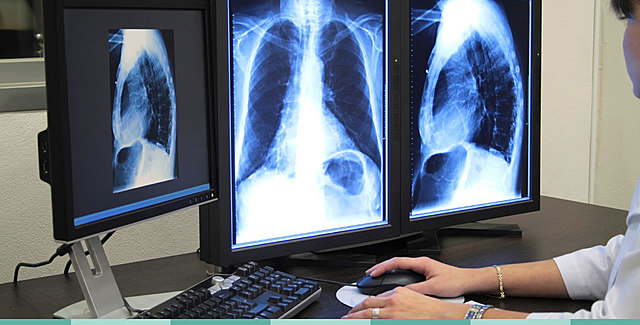

• Radiología digital

Radiología digital

Las ventajas de esta técnica sobre el chasis-película convencional incluyen mayor calidad de imagen, menor dosis de radiación

para el paciente y mayor duración de la placa